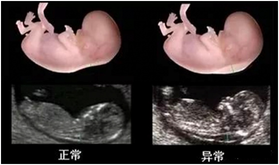

圖片3_50%.png

NT檢查(11~13+6周內(nèi))

圖片4_50%.png